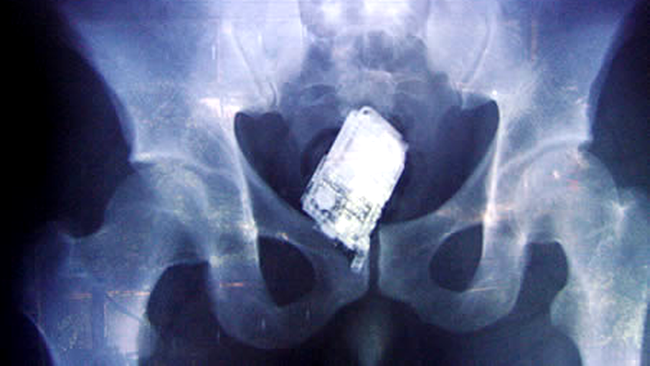

Cele mai ciudate obiecte descoperite la radiografii (Poze)

Radiologii raman uimiti cand vad in radiografia unui pacient obiecte care in mod obisnuit nu ar trebui sa se afle acolo.

Cazurile in care o persoana si-a batut un cui in cap sau in ochi, si-a introdus o sticla in anus sau a inghitit chei sunt uimitoare chiar si pentru doctori.

Medicii radiologi raman muti de uimire cand vad in radiografia unui pacient obiecte care in mod obisnuit nu ar trebui sa se afle acolo.